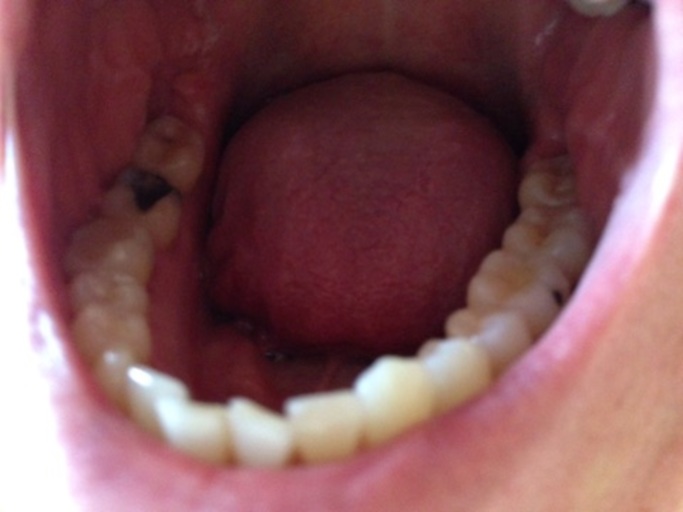

Is this a cavity in my wisdom tooth?

Hi, I am 31 and have observed a dark spot on my lower wisdom tooth (the tooth behind the one with the large silver filling on the picture). All my wisdom teeth have erupted quite good, but short after eruption I had small cavities which were filled...